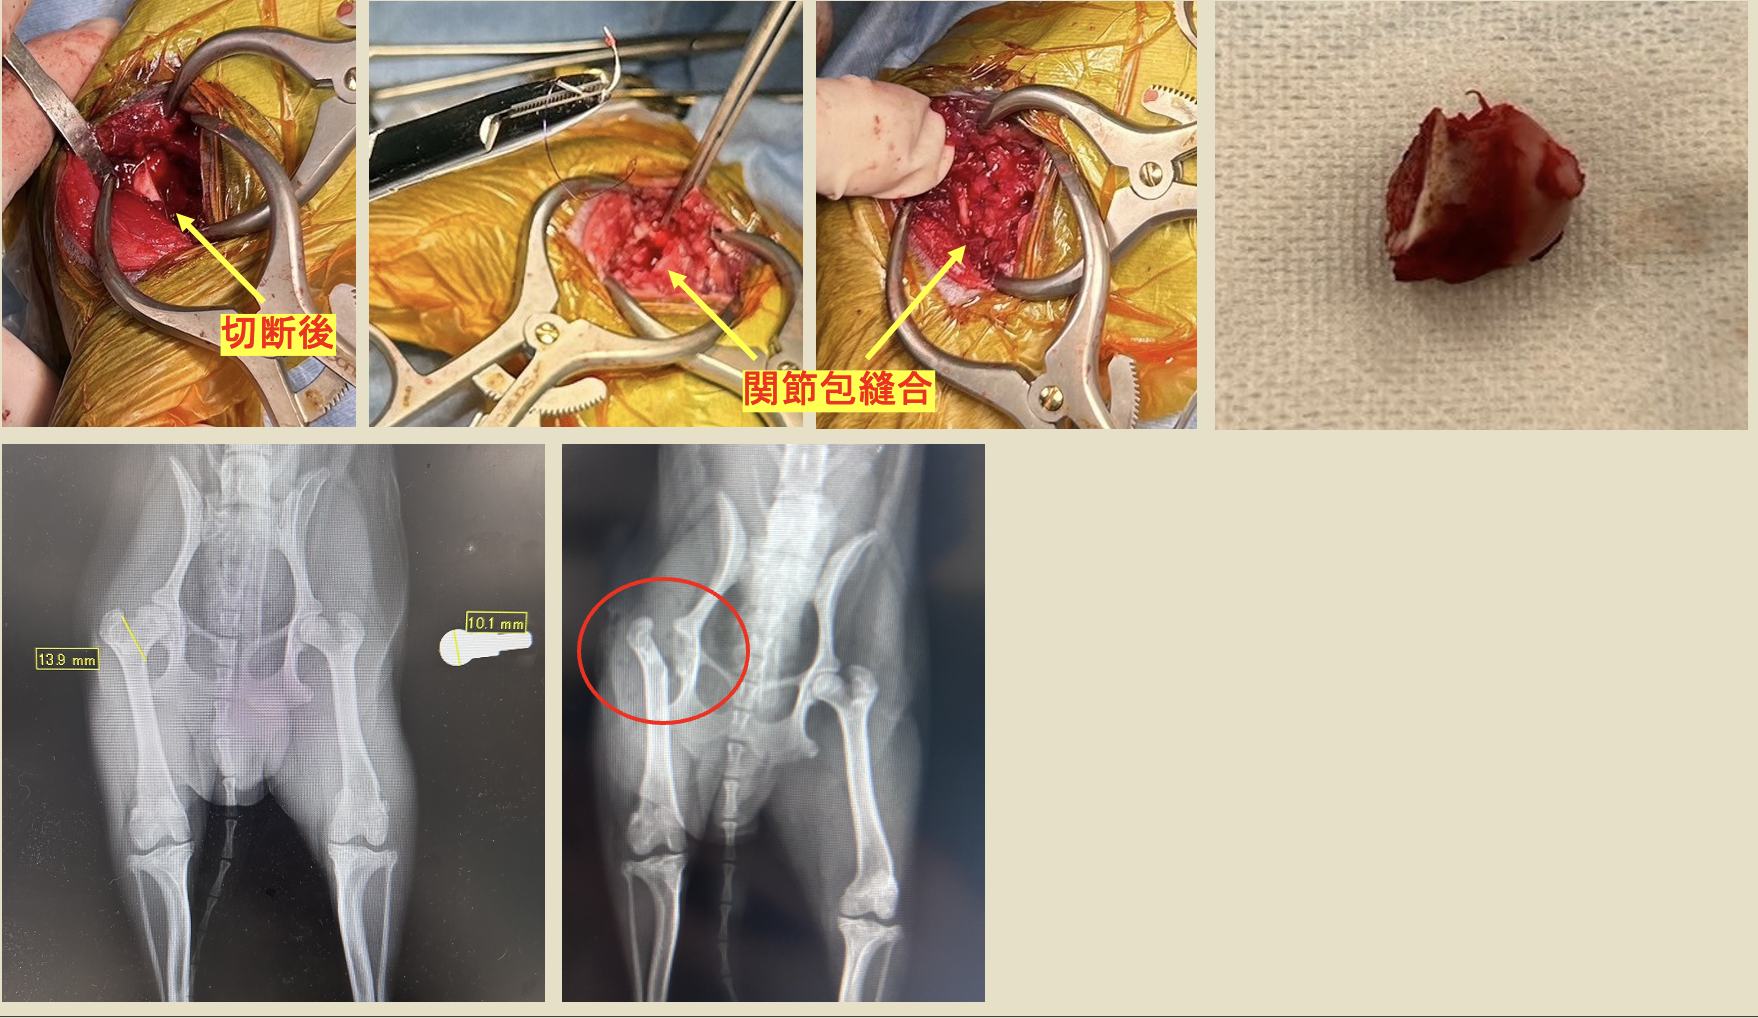

整形外科